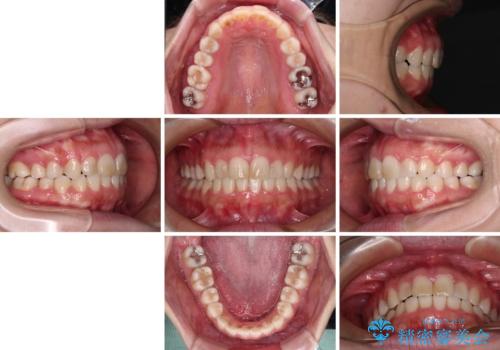

- ワイヤーではない矯正治療があると聞いたとのことで来院された患者様です。

長年前歯のデコボコを気にしていたもののワイヤー矯正に抵抗があり躊躇していたそうですが、インビザラインなら治療してみたいとのことで相談にいらっしゃいました。

インビザライン適用の歯列であったため、歯と歯の間を削るIPRを用いて改善することとしました。

お仕事柄、長時間のマウスピース装着が苦ではなかったので、歯列はすぐに整いましたが、ゆっくりとした交換頻度であったので、2年ほどの治療期間を要しました。